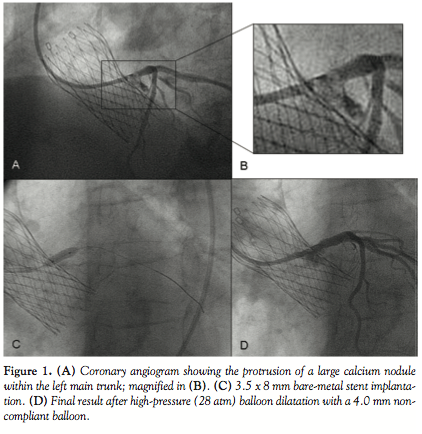

changes. On the basis of clinically suspicious and recurrent symptoms, we performed a coronary angiogram (Figure 1). Coronary angiography showed a severe stenosis of the left main trunk caused by the protrusion of a large calcium nodule of the native valve, which was compressed behind the bioprosthesis. We were not able to advance an intravascular ultrasound (IVUS) probe through the lesion at this stage. The patient was treated with a 3.5 x 8 mm stent, post-dilated

with a non-compliant 4.0 mm balloon inflated at very high pressure. Final IVUS examination is shown in Figure 2. A follow-up coronary angiography was planned after 4 months and Figure 3 summarizes angiographic and IVUS findings. There was clear recoil of the stent caused by external compression from the calcific native valve cusp, with an extreme lumen eccentricity documented by IVUS. In order to increase the radial force of the stent, we implanted a second stent within the previous one. Despite several high-pressure inflations with a non-compliant balloon, the final result was suboptimal (Figure 4). A second angiographic evaluation planned 9 months later confirmed the persistence of a mild narrowing of the left main ostium without significant neointimal hyperplasia.